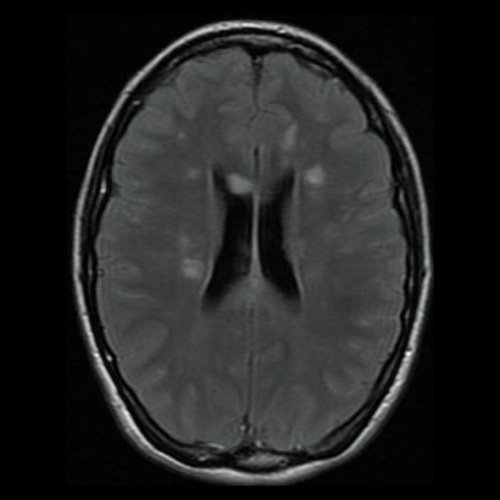

Día 2: RMI de cráneo (T2 Flair-corte axial). Lesiones hiperintensas nodulares sólidas en sustancia blanca en centros semiovales y cuerpo calloso.

La RMI muestra lesiones hiperintensas en T2 y FLAIR a nivel periventricular y subcortical, incluido el cuerpo calloso y el centro semioval, así como en la sustancia gris, incluida la corteza, los ganglios basales y el tálamo. Las lesiones infratentoriales en el tronco encefálico, el cerebelo y la médula espinal son comunes. Suelen tener realce con gadolinio. Difusión restringida.